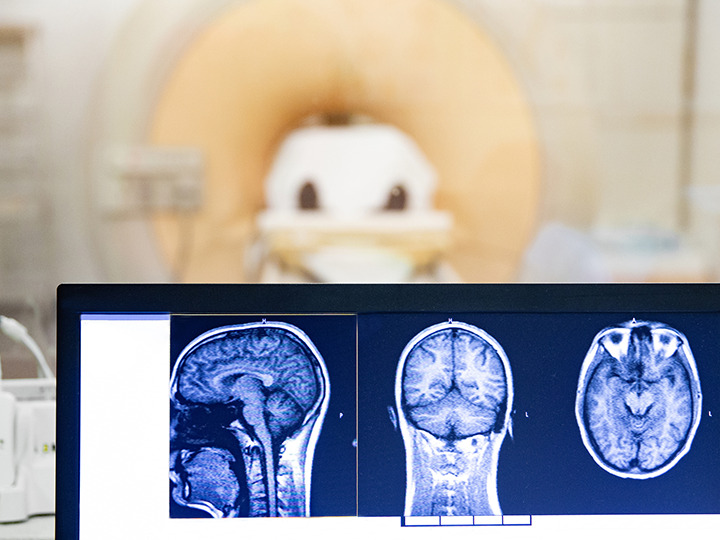

What causes epilepsy? There are many different causes of epilepsy, including genetic conditions, developmental brain abnormalities, and brain scars from prior infection, trauma or prolonged febrile seizures. In addition to these common causes of epilepsy in children and young adults, many neurological disorders seen in older adults including stroke, brain tumor and dementia are also associated with epilepsy. Standard out-patient testing that includes a high-quality MRI and EEG can often confirm the source of seizures.